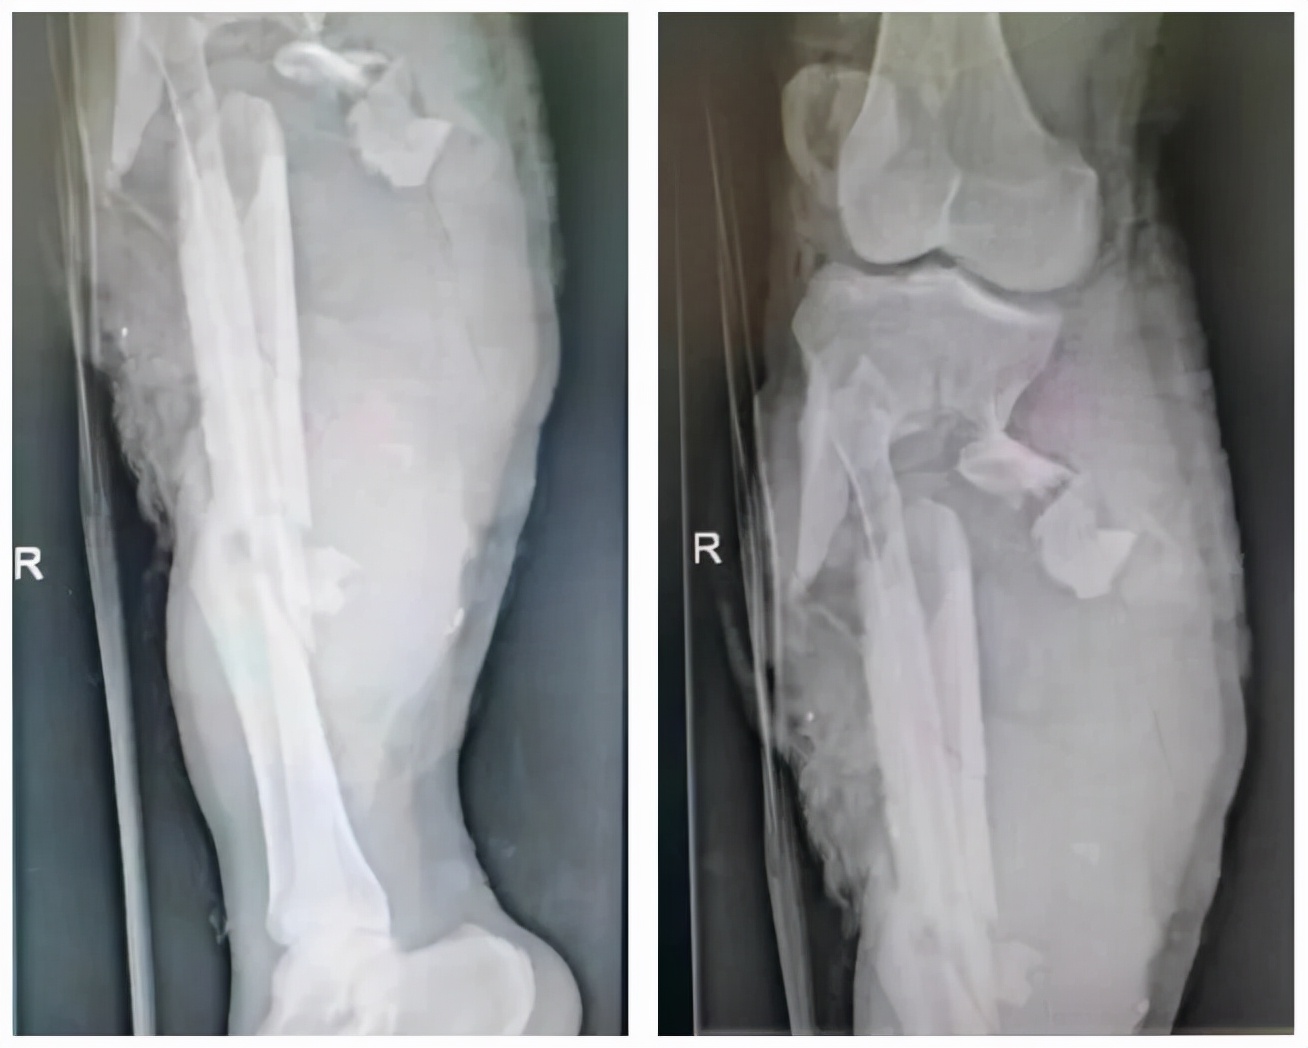

受伤后的荆某被120紧急送入威海市立医院急诊就诊,X线检查:右侧胫骨粉碎性骨折并软组织严重损伤。急诊初步包扎固定后,紧急向创伤骨科主任肖红强汇报病情,肖主任了解病情后当即组织创伤科救治小组,考虑患者正值壮年,评估病情后决定全力为患者保肢手术,术中诊断:右侧胫骨开放性粉碎性骨折,右侧小腿血管、神经损伤,右小腿皮肤、肌肉软组织毁损伤,右胫前肌、趾伸肌部分缺损,右小腿皮肤缺损。

资料片